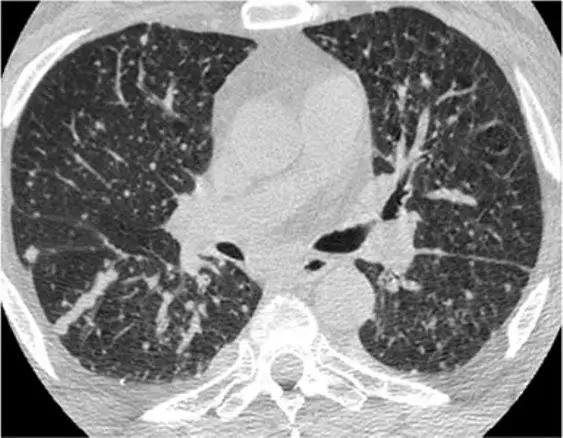

5、磨玻璃影-网状影混杂模式

有时,在肺部同一区域中可能同时存在磨玻璃样影和网状影共存,这种组合几乎等同于不可逆的纤维化。典型疾病:是非特异性间质性肺炎(NSIP)。表现为磨玻璃影改变为主、轻度网状改变。鉴别疾病:硬皮病、特发性肺纤维化(IPF)和脱屑性间质性肺炎(DIP)。

硬皮病的肺部侵袭类似于NSIP,因为它是最常见的组织学类型的纤维化。有利于硬皮病的主要发现是食管扩张和肺动脉扩张。

*硬皮病。下叶水平的HRCT表现为混合的“磨玻璃样和网状样”,其特征是磨玻璃样改变和牵引性支气管扩张。请注意5 mm胸膜下不受累,这是硬皮病最常见的组织学类型NSIP的特征相关性肺纤维化。

特发性肺纤维化(IPF)有时可能与NSIP难以区分,HRCT在区分IPF和NSIP方面的特异性范围为63%至70%。有利于IPF的鉴别诊断是呈现显著的网状蜂窝样改变,少许毛玻璃改变。

*IPF HRCT在肺底水平上表现出混合的“磨玻璃样和网状图案”,其特征是磨玻璃样改变的区域内可见牵引性支气管扩张和支气管扩张。少许蜂窝样改变。